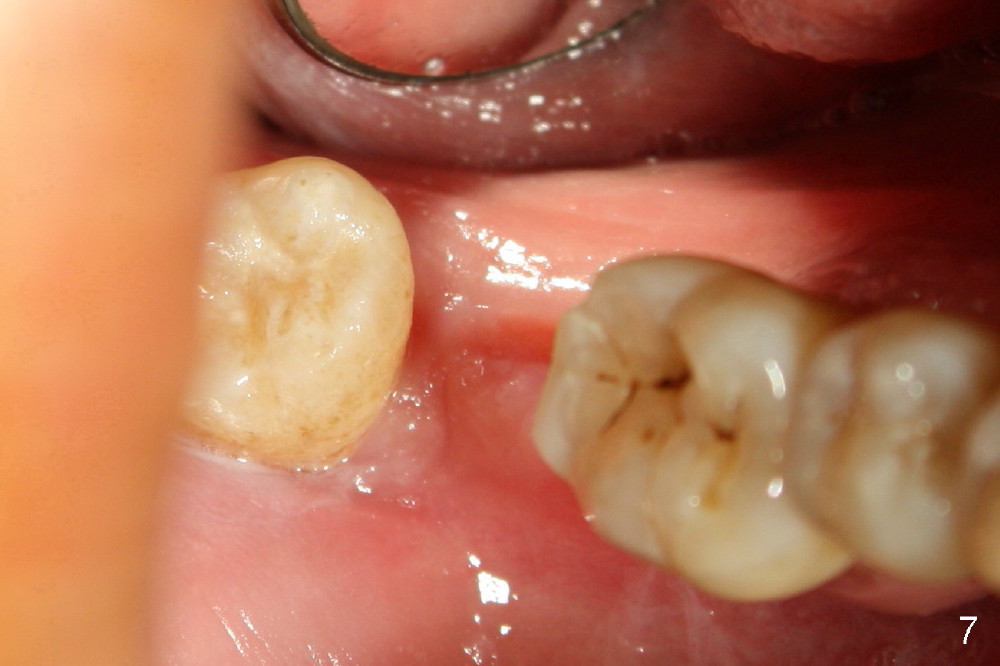

Intraop PA with a radiopaque instrument in the socket reveal the socket is large (Fig.2 arrows). The latter is filled with bone graft (Fig.3 arrows) and collagen plug (Fig.4). Fig.5 and 6 show wound healing 7 and 13 days postop. The ridge is not atrophic 4 months postop (Fig.7), ready for implant.